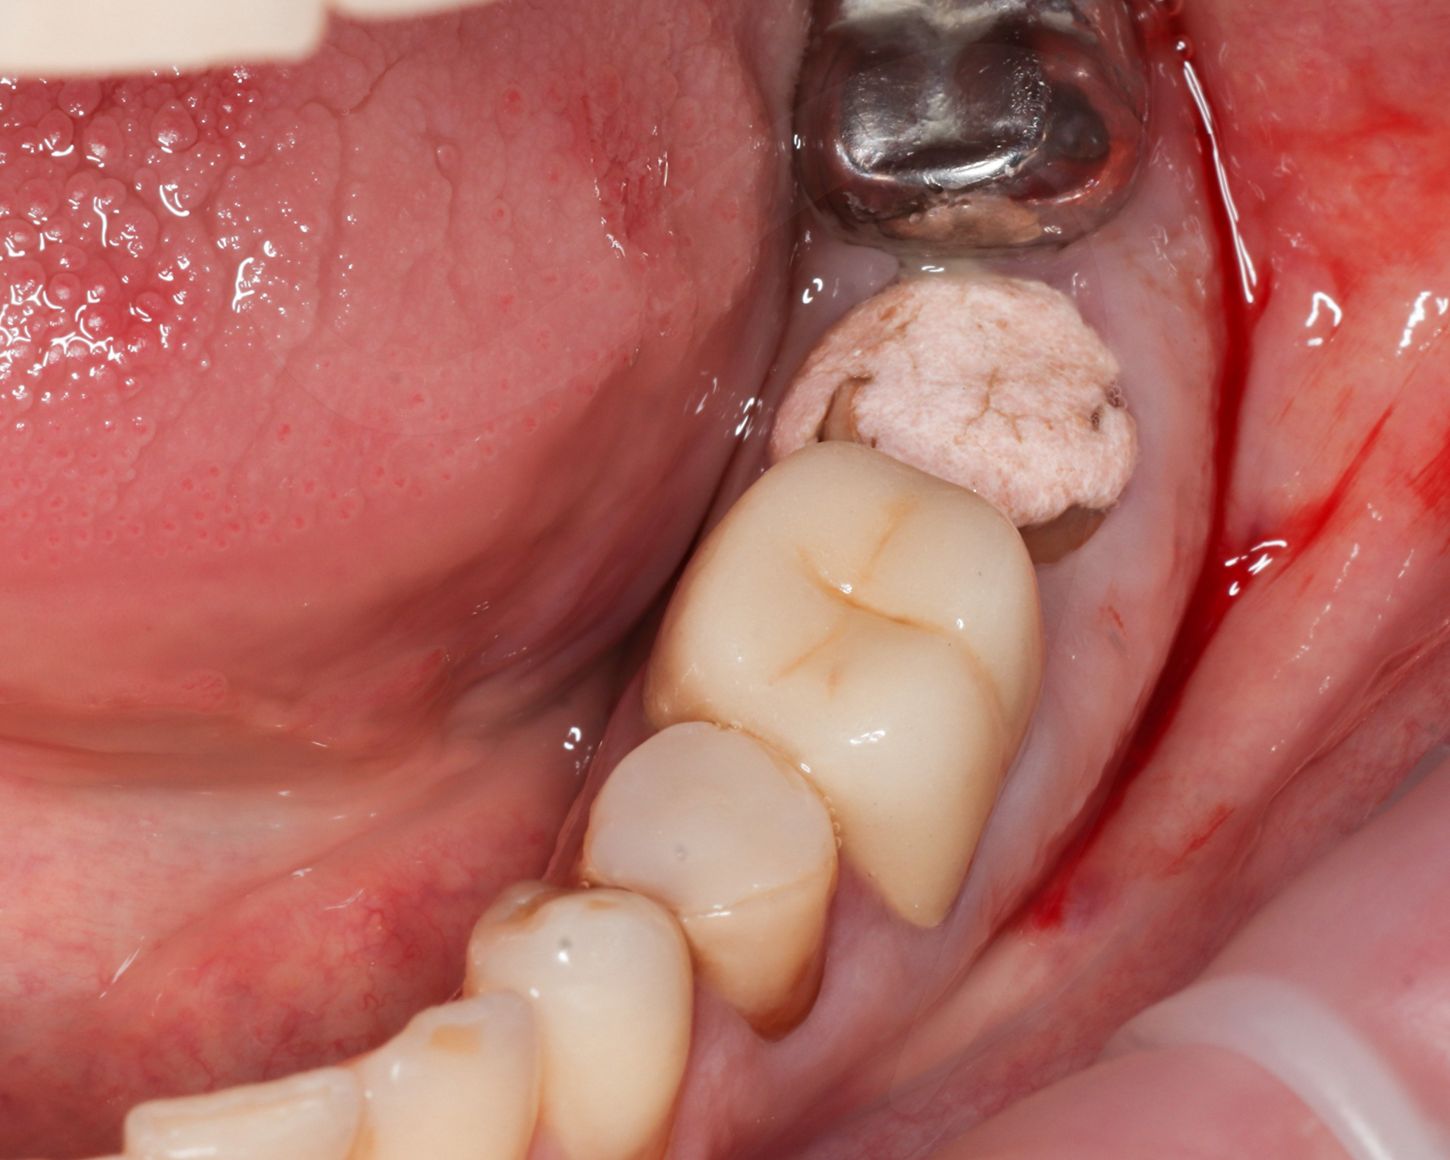

Из-за немедленной установки имплантатов между имплантатами и стенками остались зазоры, их заполнили ксенотрансплантатом.

После зафиксировали формировали десны.

Взяли трансплантат с бугра верхней челюсти и подшили в область каждого имплантата (Илл. 6-7).